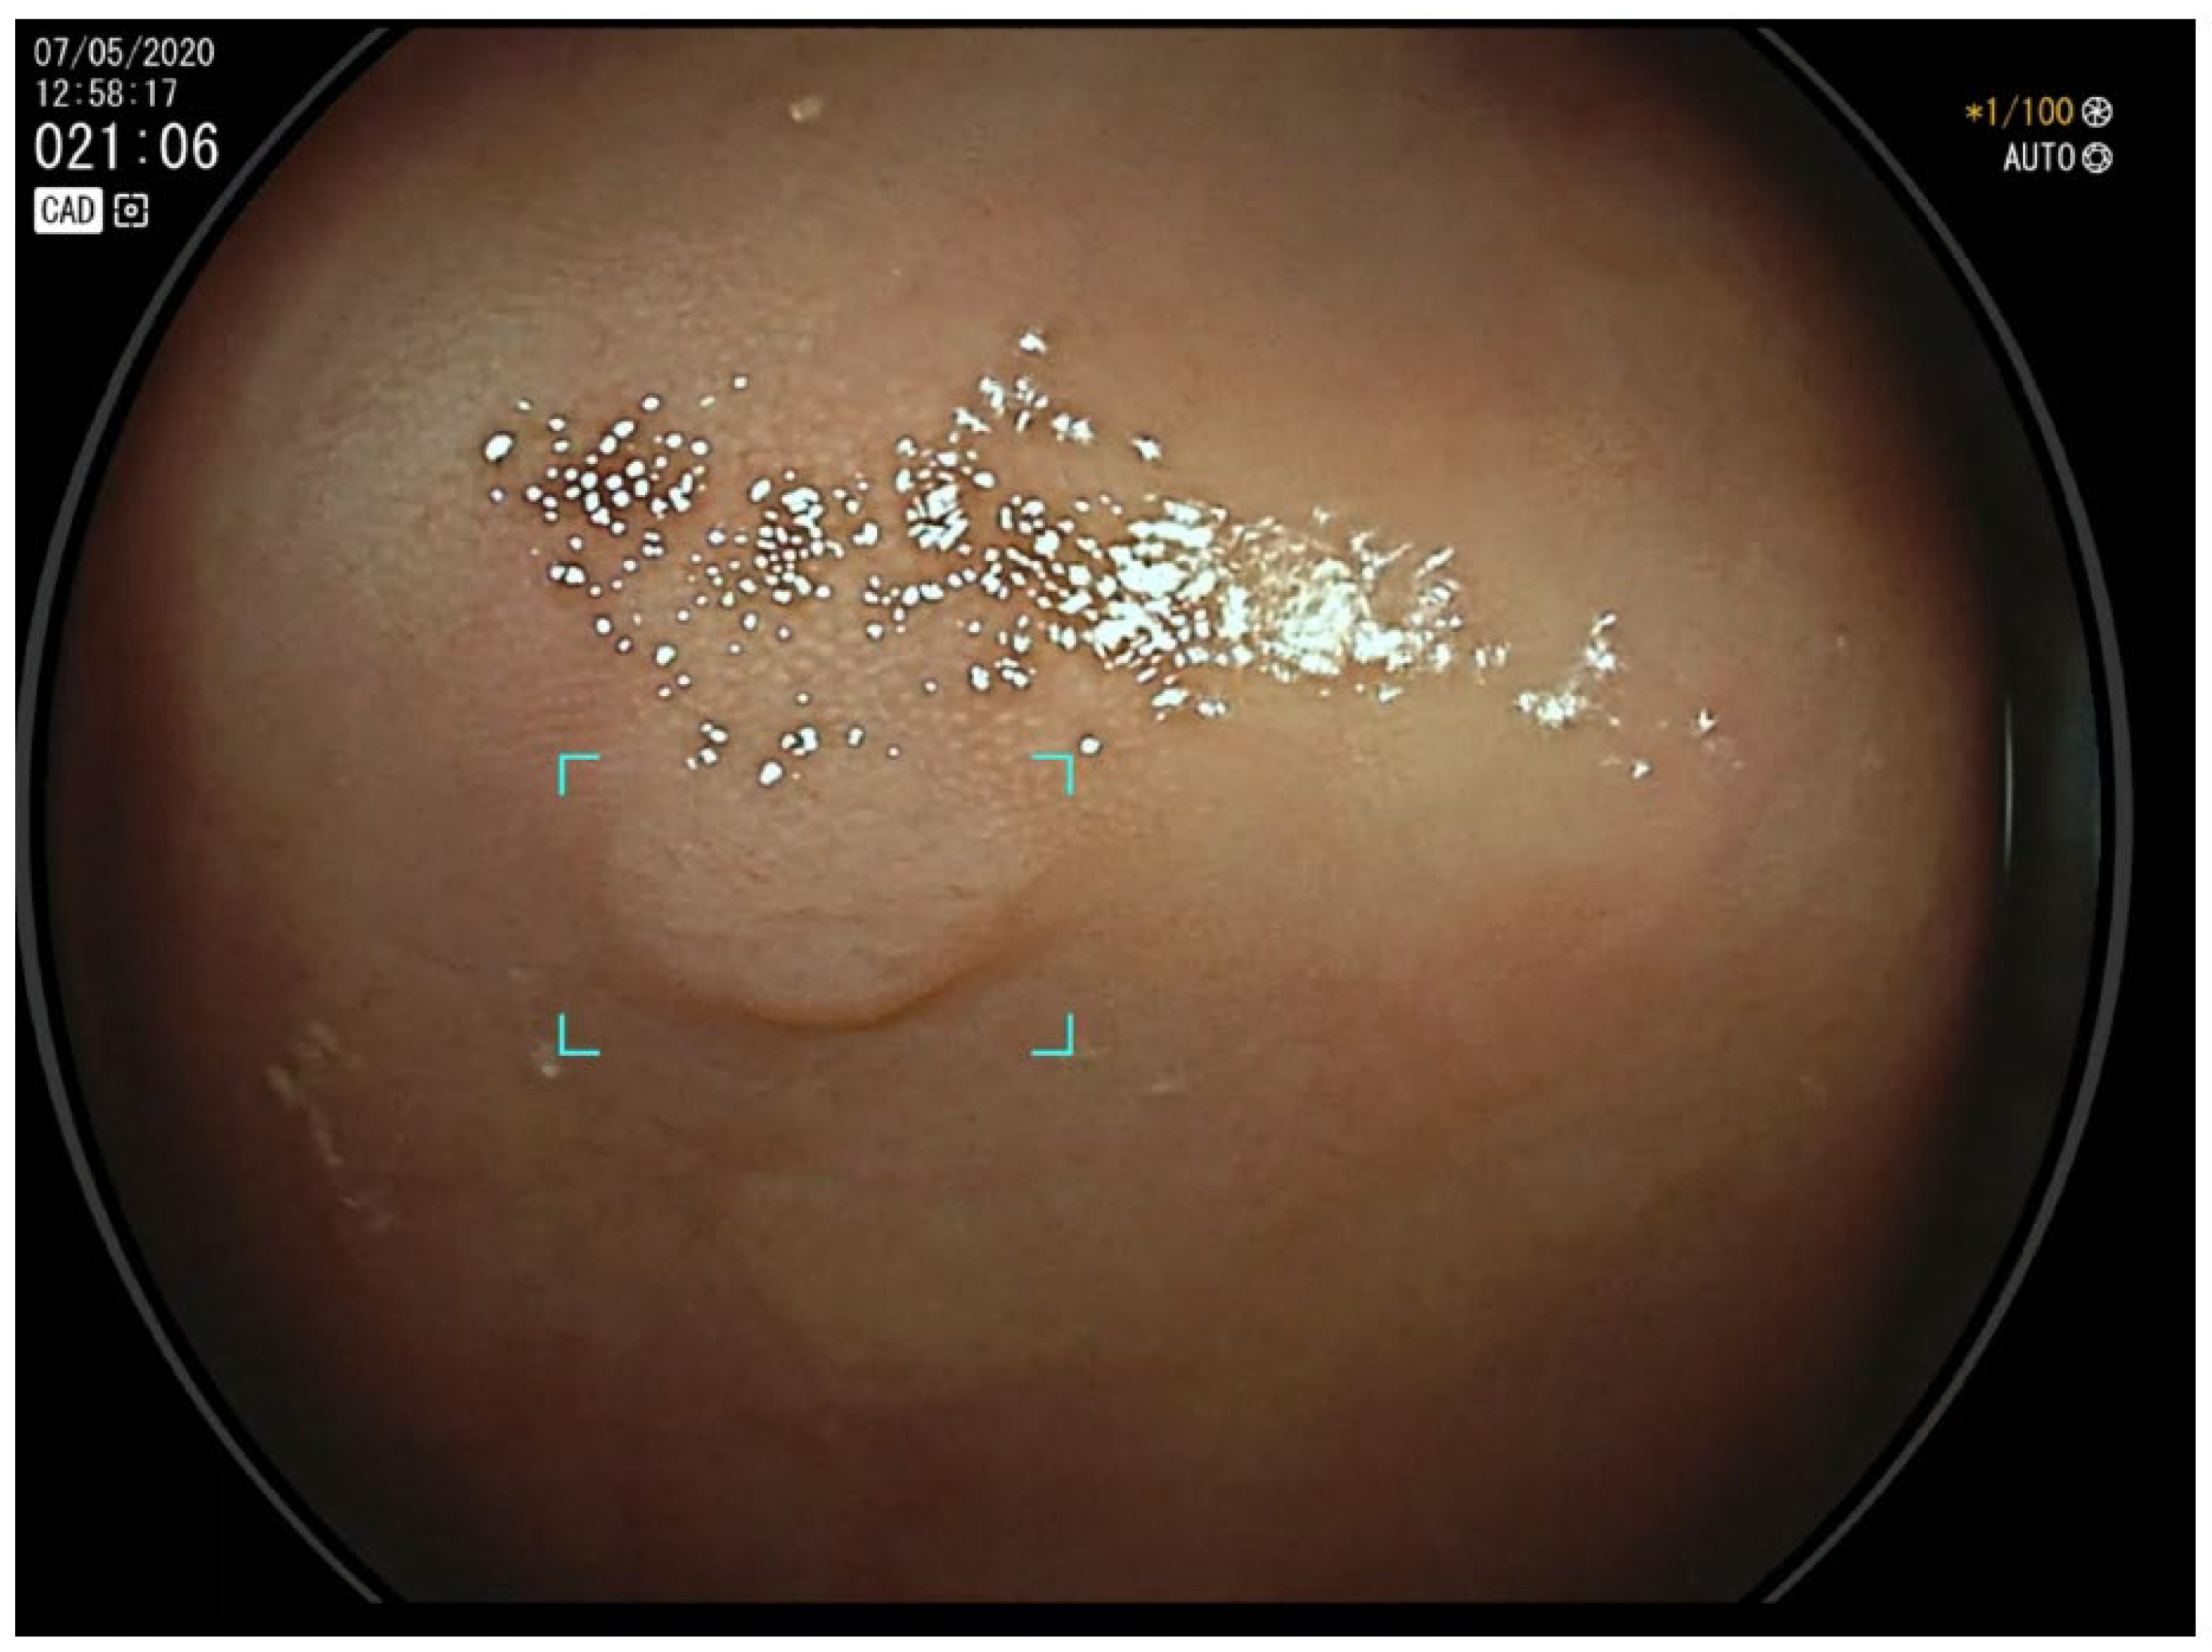

2. CADe and Adenoma Detection

4. CADe and Serrated Lesions